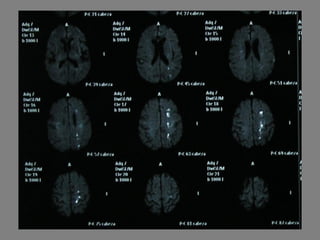

Un paciente de 75 años ingresó en el hospital debido a síntomas neurológicos como bradipsiquia, disartria y torpeza motora en las extremidades derechas que habían estado presentes durante las últimas 12 horas. Tenía antecedentes de fibrosis pulmonar e infección respiratoria reciente. El examen reveló disartria leve, paresia facial central derecha y claudicación en las extremidades derechas, lo que sugiere un posible ictus en el hemisferio izquierdo.